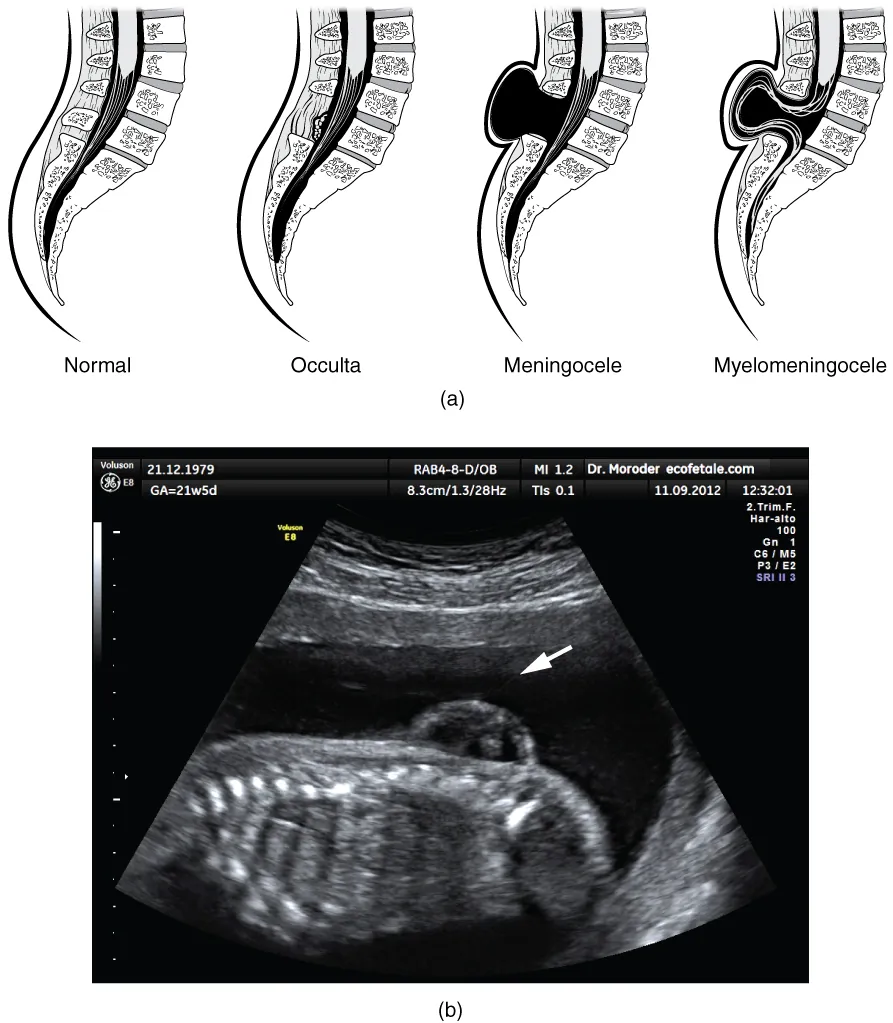

There are three classes of this disorder: occulta, meningocele, and myelomeningocele (Figure 13.5). The first type, spina bifida occulta, is the mildest because the vertebral bones do not fully surround the spinal cord, but the spinal cord itself is not affected. No functional differences may be noticed, which is what the word occulta means; it is hidden spina bifida. The other two types both involve the formation of a cyst—a fluid-filled sac of the connective tissues that cover the spinal cord called the meninges. “Meningocele” means that the meninges protrude through the spinal column but nerves may not be involved and few symptoms are present, though complications may arise later in life. “Myelomeningocele” means that the meninges protrude and spinal nerves are involved, and therefore severe neurological symptoms can be present.

This figure shows the spinal cord in spina bifida, a birth defect. In the top panel, four different spinal cords are shown. The leftmost panel shows a normal spinal cord. The remaining panels show the spinal cord in various stages of spina bifida. The bottom panel shows an ultrasound image, with a white arrow showing the region of the defect.

Figure 13.5 Spinal Bifida (a) Spina bifida is a birth defect of the spinal cord caused when the neural tube does not completely close, but the rest of development continues. The result is the emergence of meninges and neural tissue through the vertebral column. (b) Fetal myelomeningocele is evident in this ultrasound taken at 21 weeks.